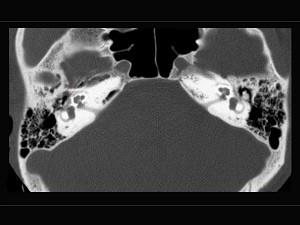

一女性患者,诉自觉听力下降,育有二子,其乳突摄片如图,可考虑为 ( )A、耳硬化症B、以上都不是C、听神经瘤D、药物性聋E、突发性耳聋

问题 一女性患者,诉自觉听力下降,育有二子,其乳突摄片如图,可考虑为 ( )

选项 A、耳硬化症 B、以上都不是 C、听神经瘤 D、药物性聋 E、突发性耳聋

答案 A